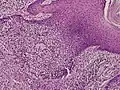

Microscopic histopathological examinations of the tumor tissues of all poroma variants stained with hematoxylin and eosin dyes reveal: a) basophilic "poroid cells" (i.e. small, cuboid-shaped cells with oval nuclei which resemble cells in the peripheral layer of the distal portion of eccrine sweat gland ducts[20]) that may form cords and broad columns extending downward from the epidermis; b) larger cuticular cells (i.e. squamous epithelial-like eosinophilic cells that resemble the luminal cells lining eccrine sweat gland ducts[20]); and in some cases c) clear cells (i.e. cells with small nuclei surrounded by pale cytoplasm).[3] Poroma tumor tissues may appear highly vascularized and/or have areas of necrosis, i.e. dead or dying cells. Hidroacanthoma simplex variants are mainly composed of poroid cells, few cuticular cells, and no clear cells and are confined to the epidermis; dermal ductal variants are mostly confined to the superficial dermis and are composed of small solid and cystic nodular aggregates of poroid, cuticular, and clear cells; poroid hidradenoma variants have large aggregates of solid and cystic components and extend deeper into the dermis or even subcutis; and eccrine poroma variants are composed of all three cell types but are primarily located in the epidermis and superficial dermis. Poromas may have 2 or more of these variants in the same tumor tissue and the variants typically have histopathology findings that are not clearly distinguishable from each other.[3]

Hidroacanthoma simplex